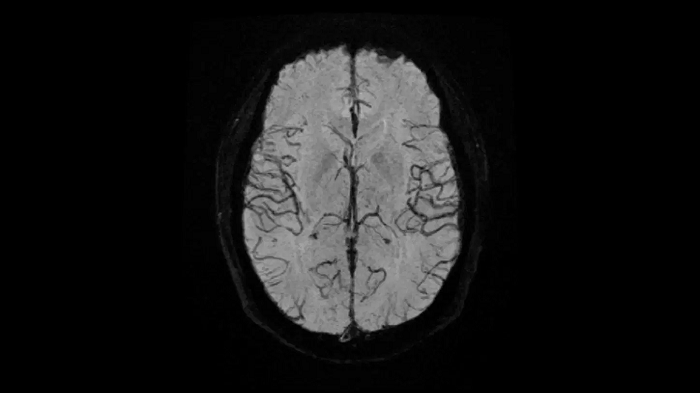

Head

EPI-based 3D SWI

A new approach towards susceptibility-weighted imaging founded on 3D EPI allows highly resolved and high-quality depiction of cranial veins on MAGNETOM Free.Max.

• Head/Neck Coil

80 cm bore MAGNETOM Free.Max

Image Courtesy: University Hospital Erlangen, Germany | Image-ID: 4aaaa0297